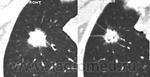

СКТ контроль через 10 дней. Получил курс  в течение 10 дней 2мя а/б в/в. Динамика слабая или нет? "Образование" подрассосалось и что получилось в итоге?

После а/б терапии признаки положительной динамики воспалительного процесса легких. Дальнейший динамический  КТ-контроль (если это возможно, т.к. были плохие прогнозы).

Понятно, спасибо. А что с "образованием"- оно заместилось небольшой полостью или что это?

Возможно наличие бронхоэктаза с частичным опорожнением содержимого; либо - формирование постпневмонического абсцесса.  Дальнейшая КТ динамика помогла бы разрешить и эту "загадку".

Итак, пророк из невролога никакой, больной не умер. Картина стала яснее,  туберкулез отошел в сторону, осталась пневмония. А "образование" стало абсцессом. Просто абсцессом, т.к. не знаю, что такое "постпневмонический абсцесс". Судя по представленным изображениям, динамика вполне положительная.

Может, в "образовании" появился распад? Нужен ли КТ-контроль и через какое время?

Наиболее вероятен постпневмонический абсцесс легкого.  Контрольное, именно, КТ-исследование  органов грудной полости через 4-5 недель после курса противовоспалительной терапии. При необходимости, по клиническим показаниям (различные виды осложнений) КТ исследование - на любом этапе лечения пациента.

"Образование" с распадом (некрозом) уменьшилось в размерах, что не характерно для C-r. Предполагаю, что все же это абсцесс на фоне полисегментарной пневмонии. Ro, КТ контроль и время сделают свои уточнения.